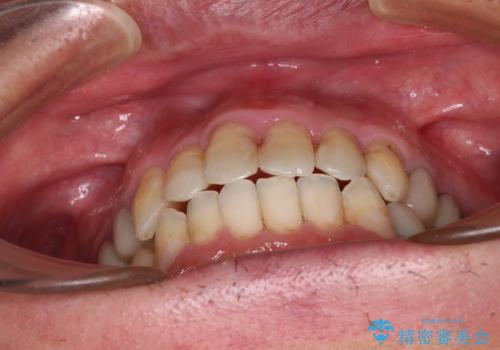

飛び出した前歯と目立つ銀歯 矯正とセラミックの総合歯科診療

- 飛び出している上顎前歯と、奥歯に多くある銀歯を気にして来院された患者様です。

マウスピースで矯正を行いたい反面、一旦早めに前歯を整えたいというご希望があったため、まずは上顎前歯をワイヤー装置で整え、その後インビザラインにて仕上げていくこととしました。

ワイヤー矯正を併用したことで、上顎前歯はあっという間に整いました。